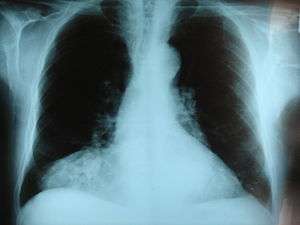

| Morgagni hernia seen on a chest radiograph. | |

This rare anterior defect of the diaphragm is variably referred to as Morgagni, retrosternal, or parasternal hernia. Accounting for approximately 2% of all CDH cases, it is characterized by herniation through the foramina of Morgagni which are located immediately adjacent and posterior to the xiphoid process of the sternum.[3]